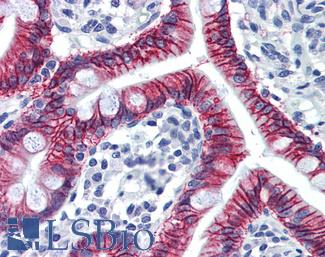

Anti-KRT20 / Cytokeratin 20 antibody IHC of human small intestine. Immunohistochemistry of formalin-fixed, paraffin-embedded tissue after heat-induced antigen retrieval. Antibody LS-B5959 dilution 1:50. This image was taken for the unconjugated form of this product. Other forms have not been tested.

CK20 (KRT20)